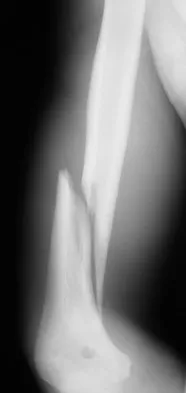

A 23-year-old man has had right posterolateral knee pain and occasional lateral calf dysesthesias for the past 8 months. A radiograph, CT scan, MRI scans, and a biopsy specimen are shown in Figures 62a through 62e. What is the most likely diagnosis?